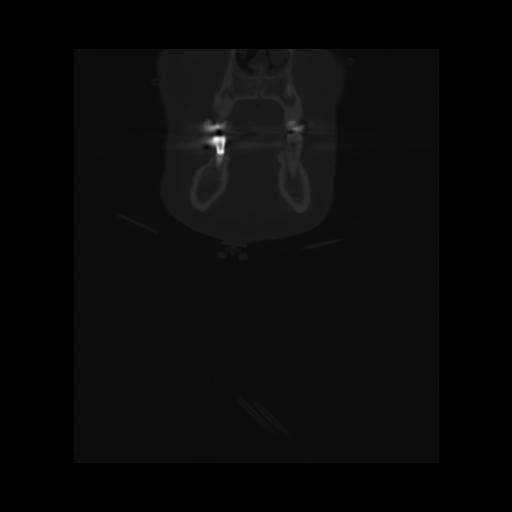

13 P.BLANDAS,,Coronal,2.000,P.BLANDAS,Coronal,